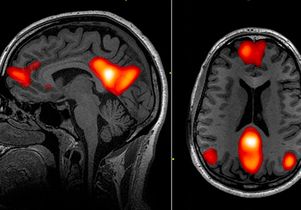

UCLA professor Jesse Rissman said the left rostrolateral prefrontal cortex is important in accessing knowledge that was formed in the past and making decisions about it.

“If the results ... are replicated in future studies, the methods we used could potentially give clinicians a new predictive tool,” said UCLA doctoral student Nicco Reggente.